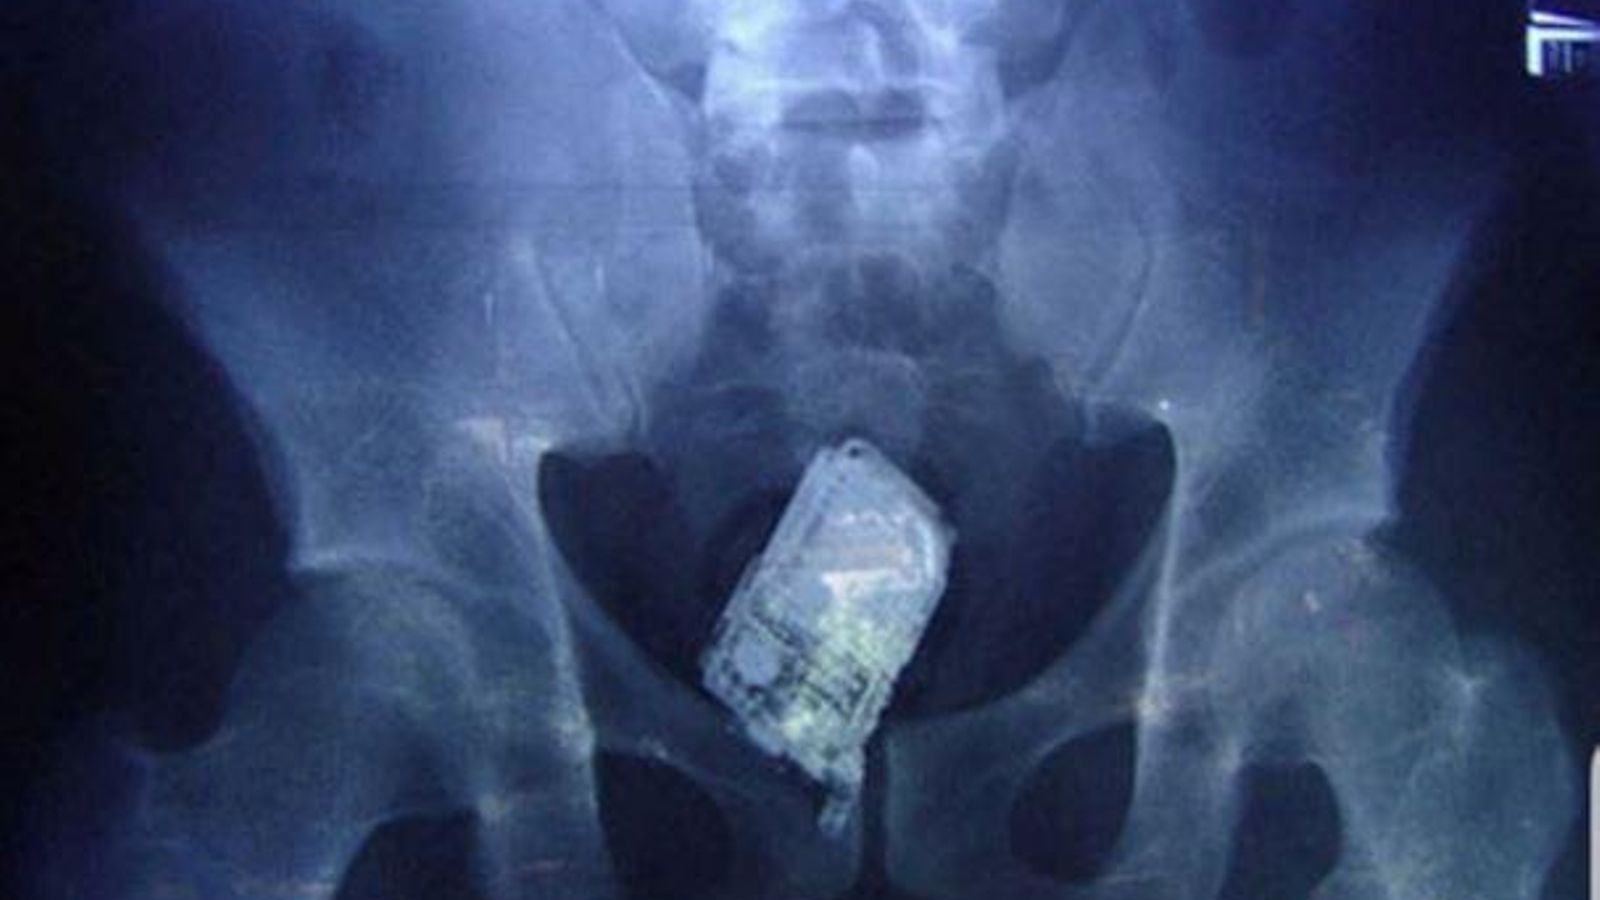

Xicotet telèfon que es va intentar introduir en la presó

Xicotet telèfon que es va intentar introduir a la presó / Acaip

Els funcionaris han de fer front a esta realitat amb mitjans clarament insuficients. Els terminals, cada vegada més xicotets i fabricats amb components plàstics, escapen fàcilment dels detectors de metalls i poden amagar-se en els llocs més insospitats.

Telèfon mòbil interceptat a Picassent

Telèfon mòbil interceptat a Picassent / Acaip